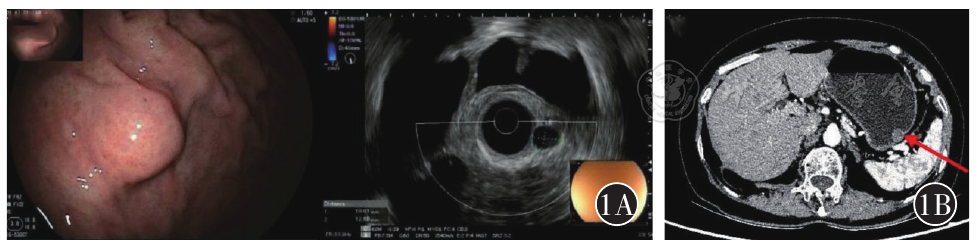

图1 A为超声内镜提示胃底大弯隆起性病变;B为CT提示胃体大弯类圆形结节